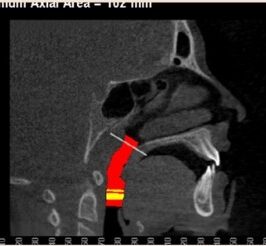

Why Airway Orthodontics

At Van Vliet & Ganz Orthodontics, we believe great orthodontic care goes beyond just straight teeth. Itโs about supporting proper function โ and that starts with how you breathe. Airway orthodontics focuses on identifying and addressing underlying issues that affect the size, shape, and function of the airway. The goal? To create space not just for teeth, but for better breathing, better sleep, and improved overall health.

This modern, holistic approach allows us to help patients-especially children-correct problems early, reduce the risk of future complications, and improve quality of life in ways that traditional orthodontics alone may not address.

For many patients, an orthodontic intervention in Highland, NY or Ramsey, NJ can improve and sometimes eliminate these risks. Below are pictures of an OSA patient that benefitted from orthodontic treatment’s life-changing effects at Van Vliet & Ganz Orthodontics.